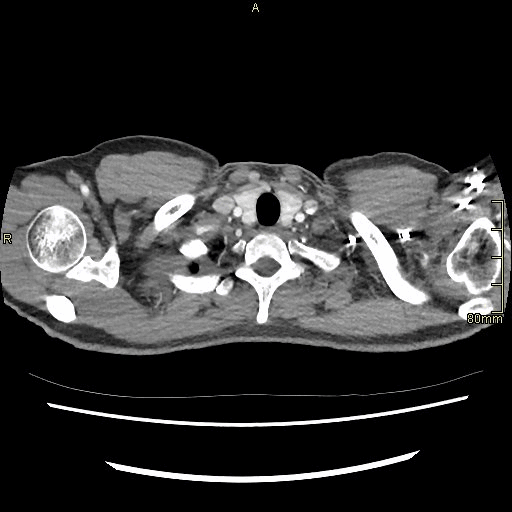

Chest Arterial (Axial)